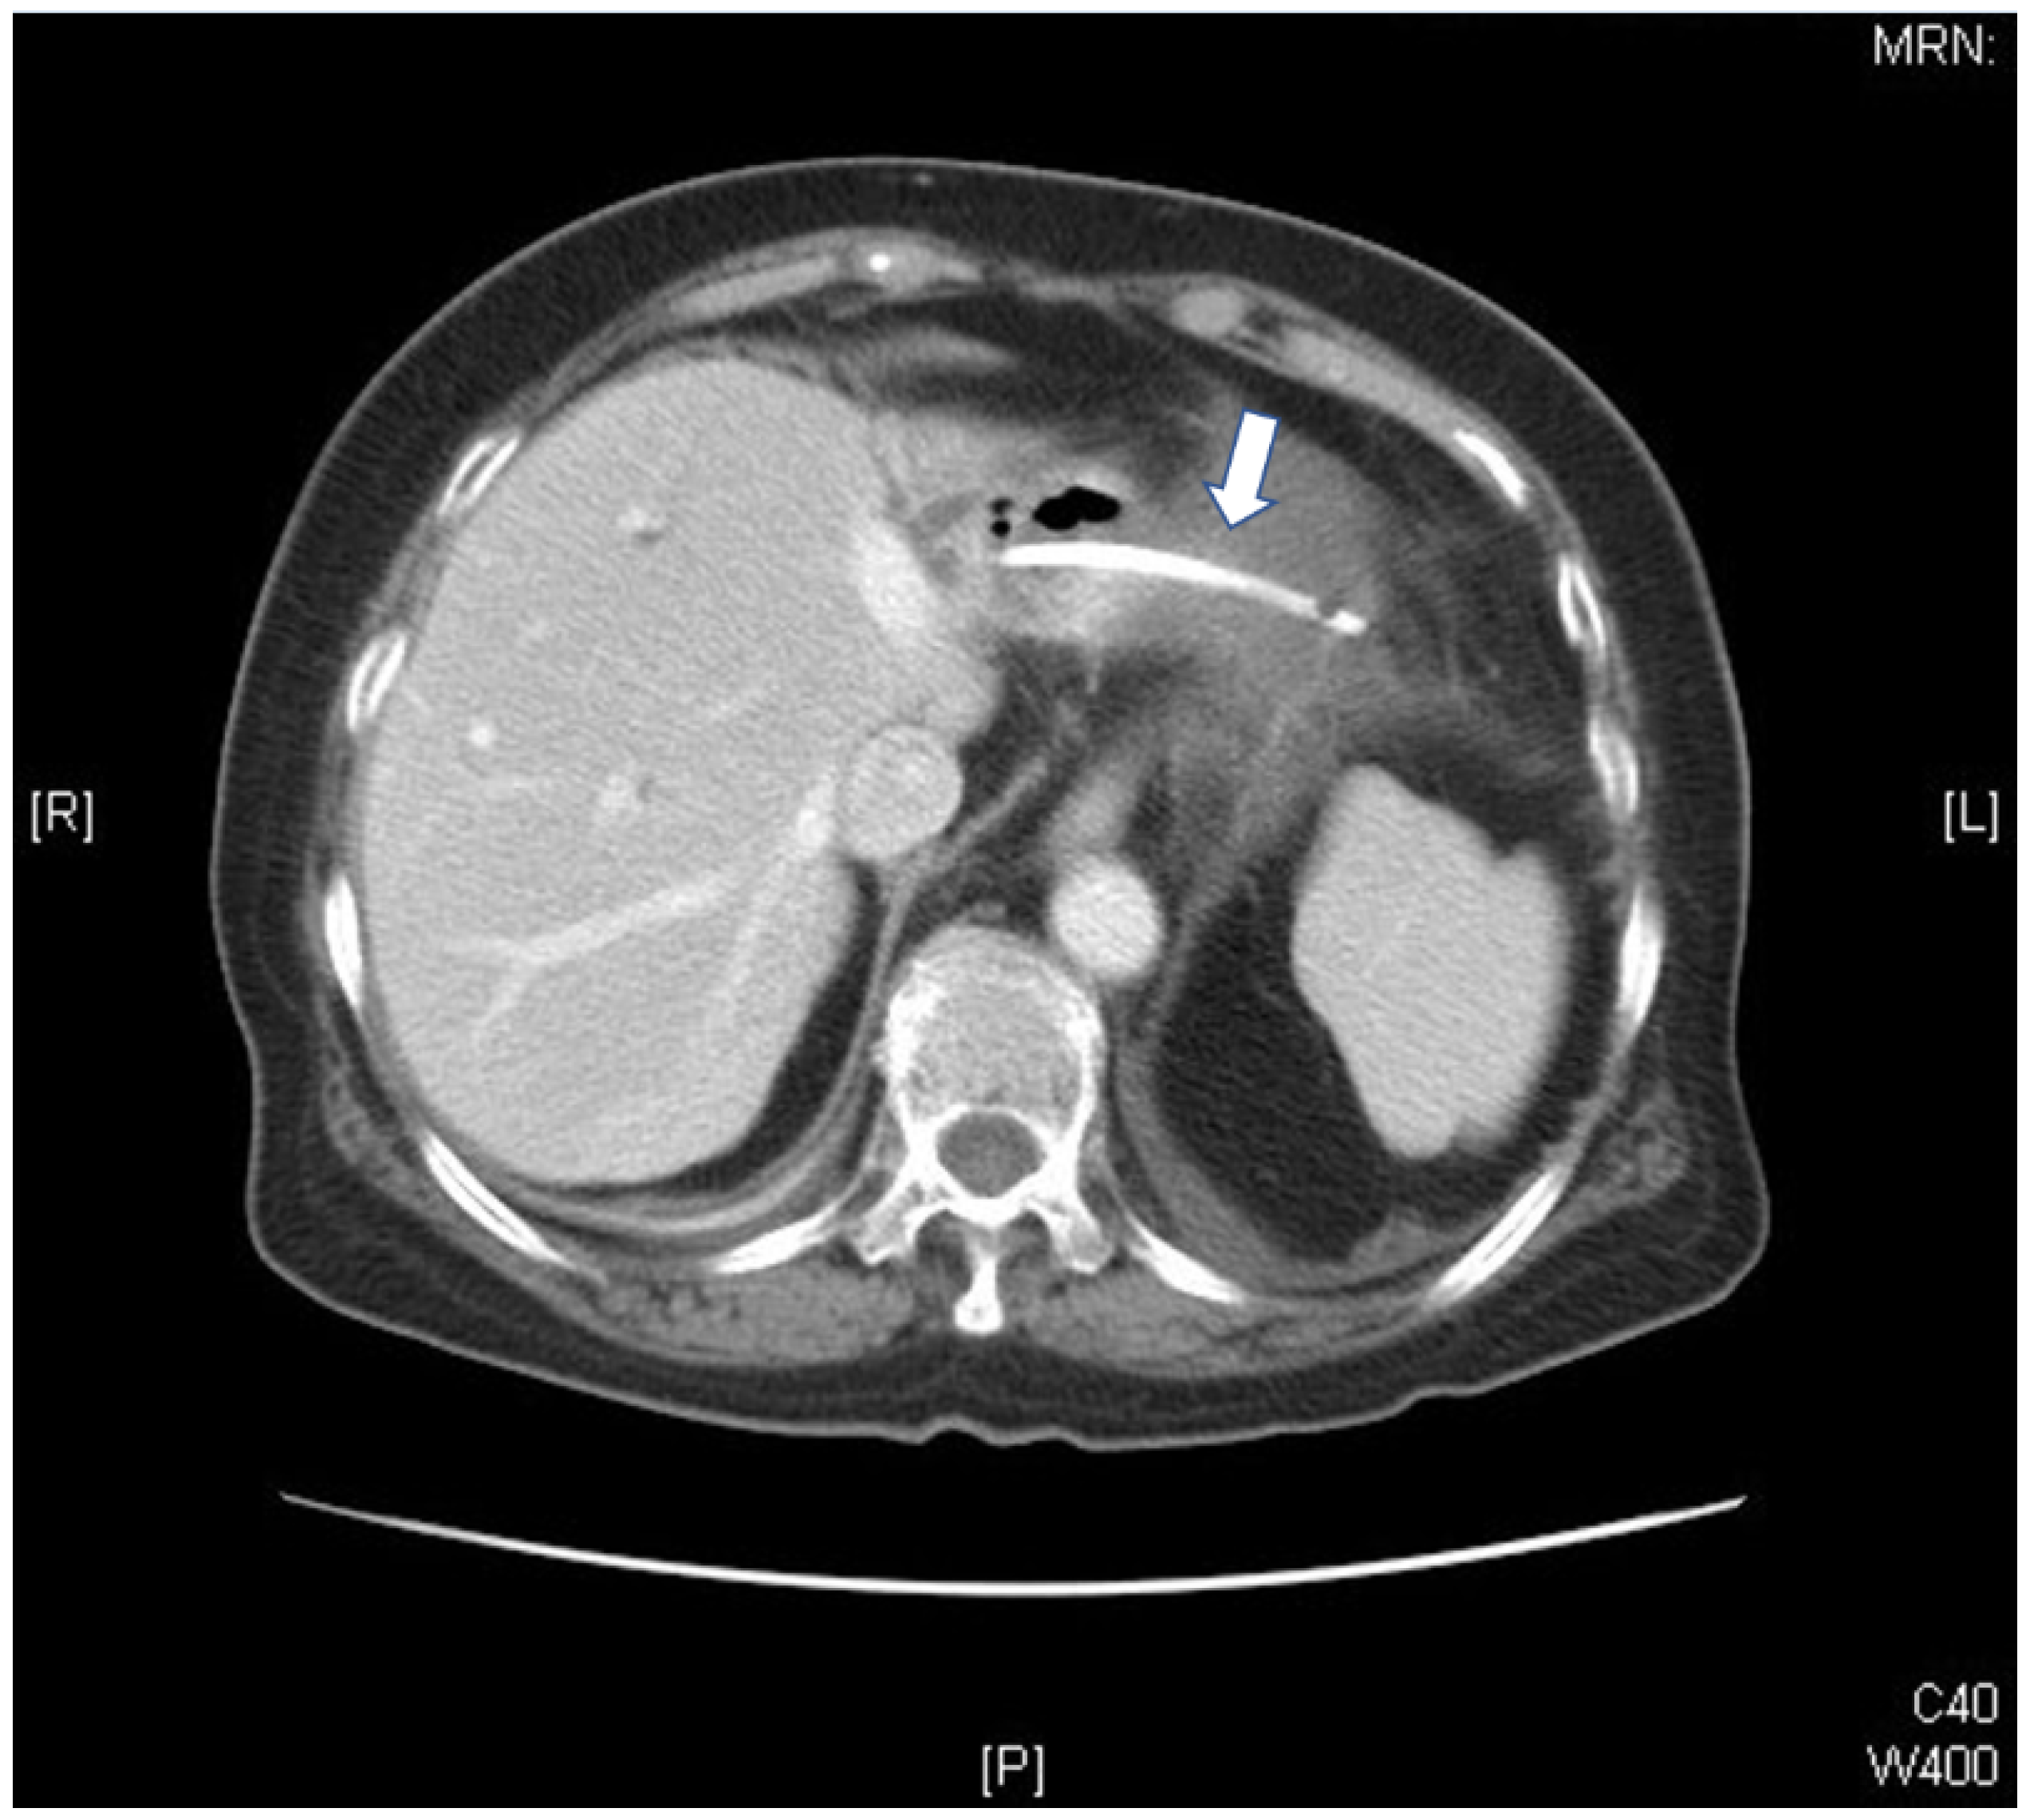

Bacterial Pericarditis Caused by Penetration of a Migrated Biliary Stent from the Lateral Segment of the Liver: A Case Report